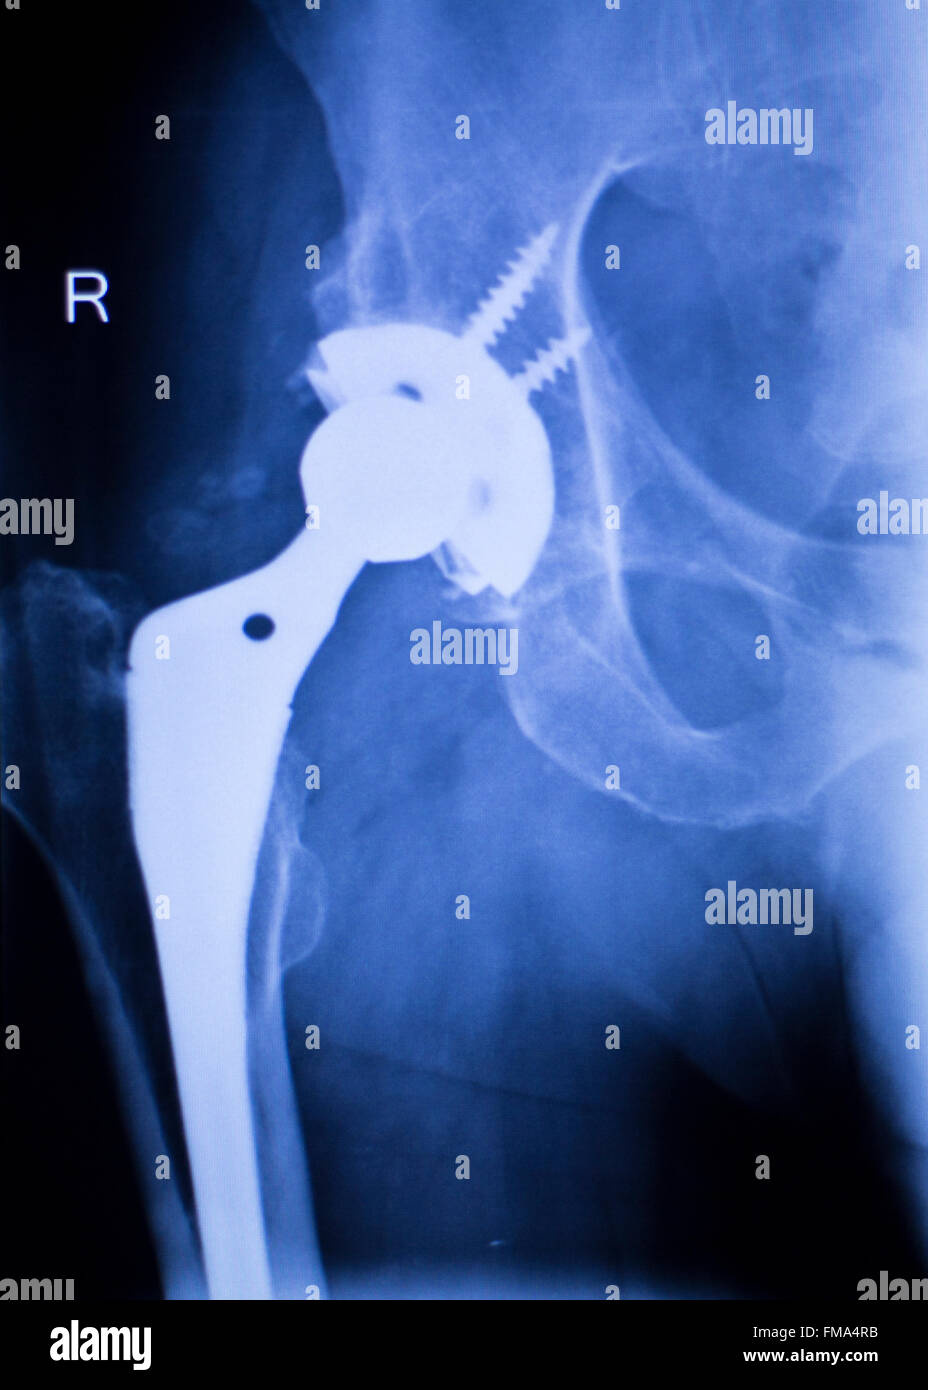

Hip replacement xray hires stock photography and images Alamy Replacement Hip Xray during hip replacement, a surgeon removes the damaged sections of the hip joint and replaces them with parts. Your orthopaedic surgeon will remove the damaged cartilage and bone and then position new metal,. radiography is the primary imaging method for the evaluation of hip arthroplasties, and imaging of a hip arthroplasty and its complications. This overview focusses on. Replacement Hip Xray.

Case Study Right Hip Arthritis with Robotic Replacement Replacement Hip Xray in a hemiarthroplasty, also called partial hip replacement, the femoral head and neck are replaced. Your orthopaedic surgeon will remove the damaged cartilage and bone and then position new metal,. This overview focusses on the normal findings and. in a resurfacing total hip arthroplasty, the femoral head. radiography is the primary imaging method for the evaluation of. Replacement Hip Xray.